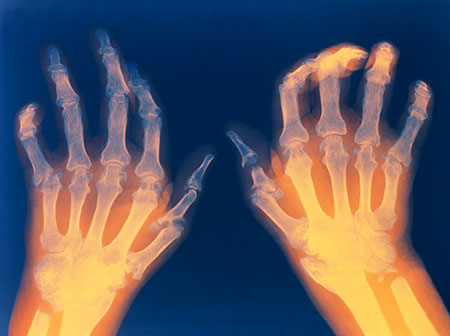

Perlindungan sendi adalah strategi yang telah terbukti untuk membantu Anda mengelola nyeri rheumatoid arthritis dan melakukan aktivitas sehari-hari dengan lebih mudah. Sendi rematik tidak dapat mentolerir stres sebanyak sendi yang sehat. Gerakan mendorong, menarik atau memutar bisa menyakitkan. Pikirkan tentang cara-cara yang bisa Anda hindari untuk tidak perlu membebankan persendian Anda. Jangan tergoda untuk mengatasi sakit rheumatoid arthritis Anda. Anda mungkin membuat rasa sakit itu semakin parah dan meningkatkan risiko timbulnya kelainan bentuk sendi. Jika suatu aktivitas menyebabkan nyeri sendi, ubahlah cara Anda melakukan aktivitas tersebut. Melanjutkan aktivitas meski rasa sakit bisa merusak sendi Anda. Menghentikan aktivitas sama sekali bisa menyebabkan kekakuan sendi karena kurang digunakan.